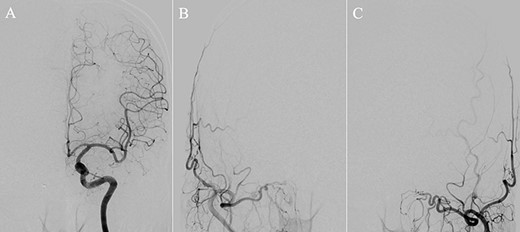

A patient in their 70s with extracranial lymphoma was incidentally found to have ACF–dAVF via head computed tomography and magnetic resonance angiography. Digital subtraction angiography (DSA) confirmed ACF–dAVF with multiple feeding branches, arising from bilateral OphAs, distal IMAs and the left middle meningeal artery (MMA), with cortical venous reflex (Borden type III, Cognard type IV) (Fig. 1). At the patient’s request, we chose endovascular, rather than surgical, treatment. We injected a 20% N-butyl-2-cyanoacrylate (NBCA)–lipiodol mixture into the fistula through bilateral ethmoidal arteries and the left MMA after we placed coils at the terminal branch of the right OphA. However, we could not achieve full penetration into the fistulous connections because of pressure secondary to high flow from the IMA branches, which resulted in incomplete obliteration (Fig. 1). Four months later, we repeated TAE by temporarily reducing nasal blood flow by inserting gauze infiltrated with xylocaine and epinephrine into the nasal cavities. After introducing the guiding catheter, an endonasal surgeon inserted X-ray-detectable surgical gauze infiltrated with 1% xylocaine and epinephrine (1:10 000) into bilateral nasal cavities using a nasal speculum, while paying full attention to avoid damage to the nasal mucosa. Then, we confirmed that the gauzes were placed in appropriate locations in the upper nasal cavity under fluoroscopic guidance. Immediately after insertion, we were able to confirm decreased blood flow from the IMA using DSA (Fig. 2). After this procedure, we navigated a DeFrictor Nano Catheter (Medico’s Hirata, Osaka, Japan) into the terminal branch of the OphA, which was connected to the dorsal nasal artery. Even though there was still a distance from the tip of the microcatheter to the shunt pouch, the NBCA reached the shunt point and penetrated the venous portion (Fig. 3). Follow-up DSA demonstrated complete obliteration of the ACF–dAVF, and blood flow in the nasal mucosa from the IMA branches recovered normally (Fig. 4).

(A) DSA, anteroposterior view, showing complete obliteration of the anterior cranial fossa–dural arteriovenous fistula. (B and C) DSA, anteroposterior view, showing restored blood flow from the internal maxillary artery branches.